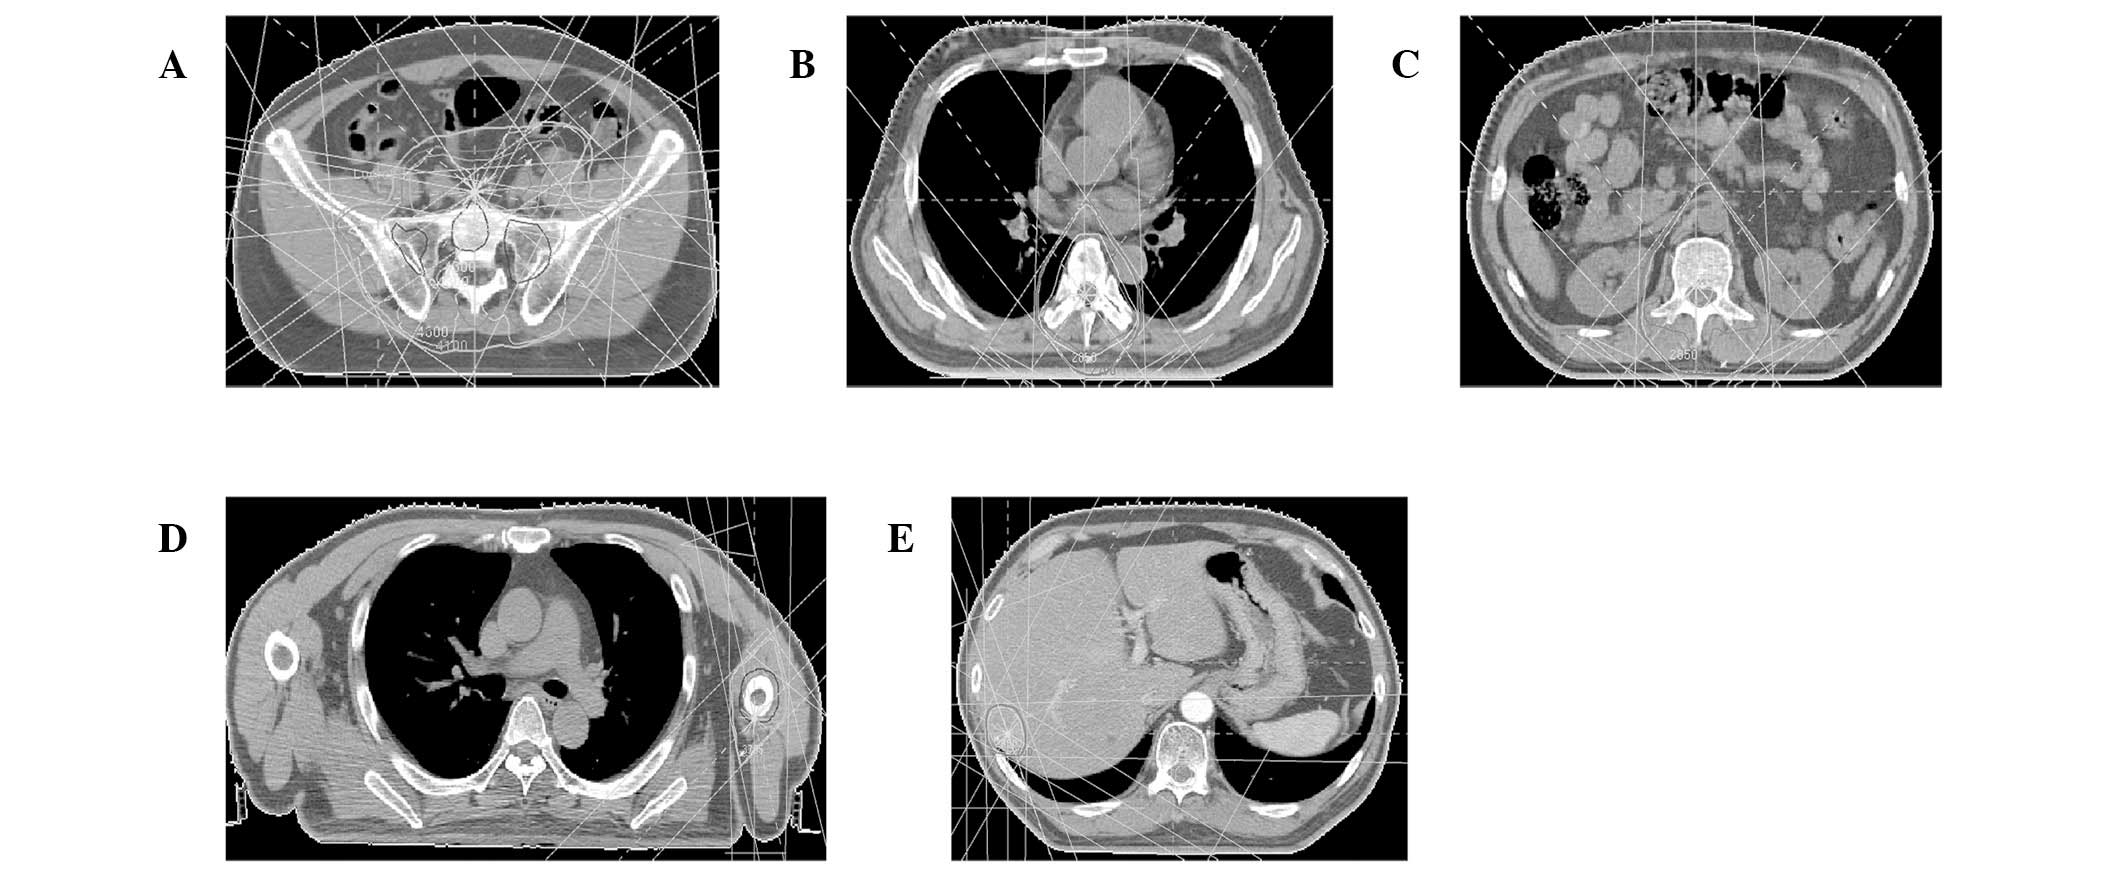

Figure 1.

Cutaneous Merkel cell carcinoma involving inguinal lymph nodes, bone, liver and humerus metastases identified by follow-up PET-CT. (A) Large lymph node metastases observed at initial presentation (large arrow). (B) Following initiation of chemotherapy (EP regimen), lymph node metastases shrunk (large arrow) but metastasis to the vertebra occurred (small arrow). (C) Following chemotherapy (IP regimen) and radiotherapy, lymph node metastases recurred and vertebral metastases shrunk (small arrow). (D) Disappearance of lymph nodes and vertebral metastases following concomitant treatment with chemotherapy (IP regimen) and radiotherapy. (E) Following 4 months of combination therapy, metastases in the liver (large arrow) and humerus (small arrow) were discovered by PET-CT follow-up. EP regimen, etoposide/cisplatin; IP regimen, irinotecan/cisplatin. PET-CT, positron emission tomography-computed tomography.

Treatment and clinical course

The patient was initially treated with a combination of etoposide (100 mg/m2, days 1–5) and cisplatin (50 mg/m2, days 1–3) every 3 weeks. A partial response was achieved in the LNs but progressive metastatic disease was present in T6 and T12-L2 following two cycles (Fig. 1B). The patient then received chemotherapy with irinotecan (100 mg/m2, day 1, 8, 15) and cisplatin (40 mg/m2, days 1–3) every 3 weeks as well as RT with 54 Gy/30 fractions/6 weeks to inguinal LNs (Fig. 3A) and 30 Gy/10 fractions/2 weeks to T6 and T12-L2, respectively (Fig. 3B and C). A partial response was achieved following two cycles (Fig. 1C).

The patient tolerated only two cycles of chemotherapy concomitant with RT, following which his condition deteriorated due to grade IV bone marrow suppression and poor performance status. Thereafter, the patient was treated with a third cycle of chemotherapy with reduced concentrations of irinotecan (70 mg/m2, days 1, 8, 15) and cisplatin (30 mg/m2, days 1–3). Following five cycles of chemotherapy concomitant with RT, the mass in his right groin resolved, the metastatic diseases disappeared and complete response was observed (Fig. 1D).

The patient demonstrated no evidence of disease for 4 months when a subcutaneous mass was identified. Subsequently, PET-CT follow-up revealed that the patient’s liver and humerus had metastatic disease (Fig. 1E). Mohs micrographic surgery and salvage chemotherapy plus RT (Fig. 3D and E) were then instituted, but the patient succumbed to liver failure 21 months following the onset of his illness.